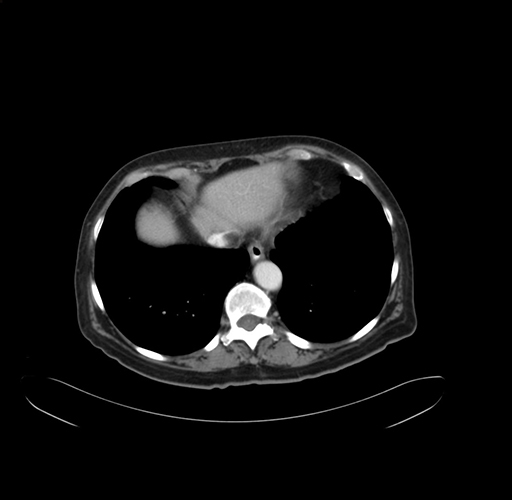

Pre-Chemo: Axial Venous